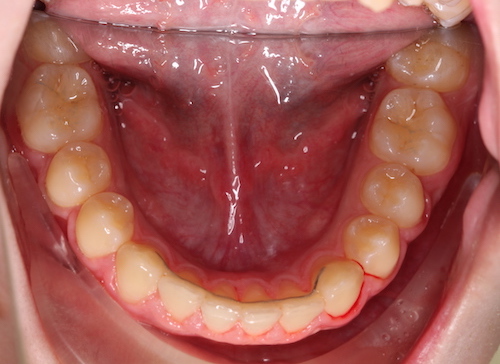

До